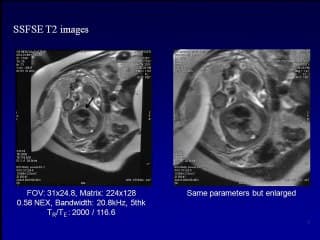

L'auteur décrit les avancées de l'IRM pour l'exploration du cœur fœtal en complément de l'échographie cardiaque qui reste bien sur la technique de référence. On peut imaginer son apport dans les situations de difficultés pour l'échographie comme l'obésité maternelle ou l'Oligoamnios, mais des progrès et une évaluation multicentrique sont encore nécessaires.